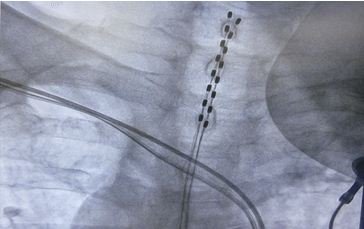

1. 脊髓电刺激  SCS装置包括两根电极导线和脉冲发生器。通常在局麻的条件下,将电极植入硬脊膜外腔T1-T2的水平,如图5-4-2所示,然后通过皮下隧道连接位于腰部或腹部的脉冲发生器。一般于术后第一天通过程控仪进行测试,以调整脊髓刺激的具体参数。患者亦配备简易程控仪,可调整强度等少部分参数,以提高患者的舒适度。另外,目前开发的SCS是可充电式的系统,可以经过皮肤对植入的脉冲发生器进行充电,在提高输出刺激参数的同时,大大延长了脉冲发生器的使用寿命,降低了患者的治疗费用。

http://webres.medlive.cn/upload/000/142/565

图5-4-2 SCS装置中两根电极植入硬脊膜外腔T1-T2的水平